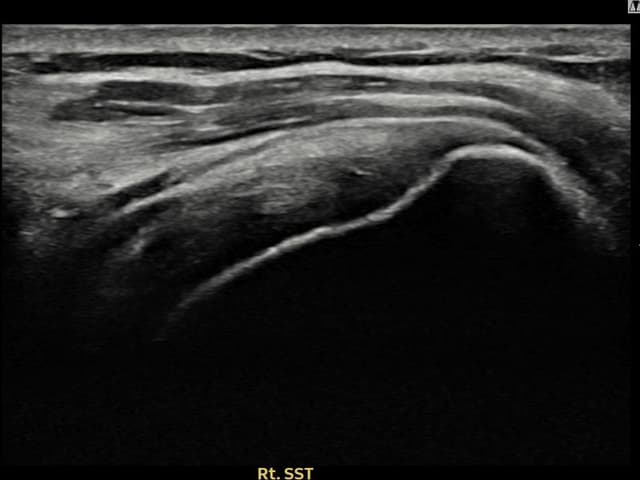

[촬영시기:23.09.01~23.11.03]

[어깨인대 축소봉합술] 우측 어깨 통증이 수개월간 지속되어 내원하셨습니다.